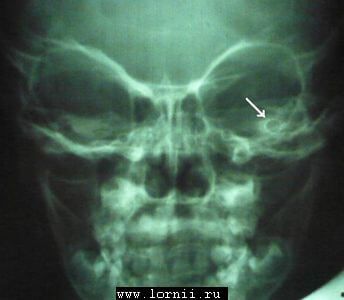

Послеоперационная трансорбитальная рентгенография улиток выявила, что активный электрод импланта находится в общей полости (рис. 4, стрелка), приняв форму идеальной окружности.